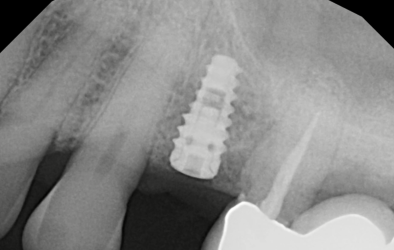

I do have more x rays that I’ll attach here.